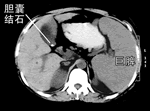

解放军总医院腔镜中心经腹腔镜成功切除巨脾及胆结石

本报讯 (驻地记者 姚春雨 钱勇)日前,解放军总医院肝胆外科主任周宁新教授等,经腹腔镜成功为1例女性患者切除了23 cm×20 cm的巨大脾脏和胆囊结石。患者因原发性脾亢、胆囊结石入院,周教授和蔡守旺医师等为患者实施了经腹腔镜手术,获得成功。, 百拇医药